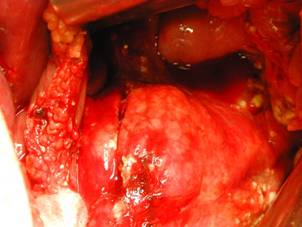

Aspect postsplenectomie Hematom subcapsular

splenic rupt